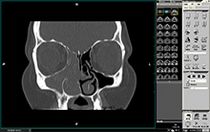

Einseitige Verschattung der rechten Kieferhöhle, des Siebbeins und der Nasenhaupthöhle (Rhinopapillom) (Computertomographie, CT)